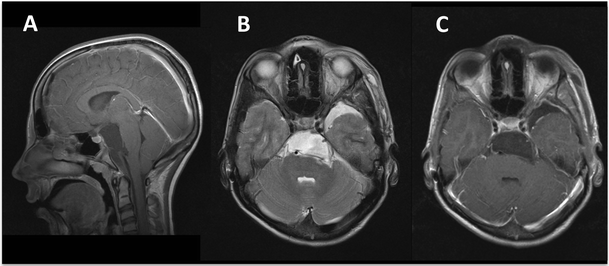

Postoperative MR images. A complete tumour removal is shown on the a parasagittal T1-weighted sequence, b axial T2-weighted sequence and c axial T1-weighted sequence after administration of gadolinium contrast